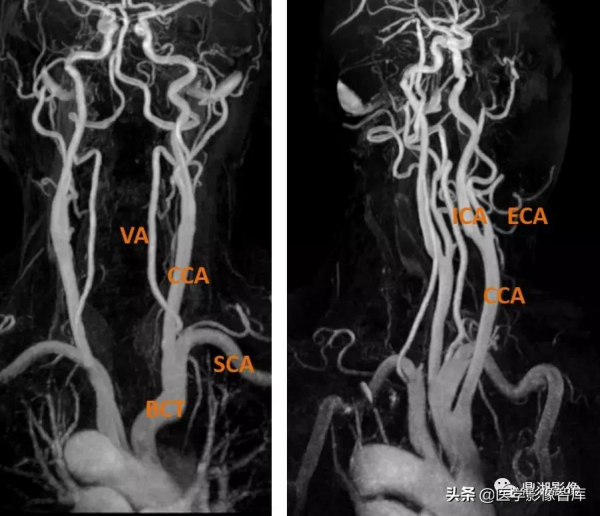

頸部及顱內血管

主動脈弓分支(2/3)

無名動脈(頭臂幹, brachiocephalic trun,BCT)-右側頸總動脈RCCA、右側鎖骨下動脈RSCA

左頸總動脈(left common carotid artery,CCA)

左鎖骨下動脈(left subclavian artery,SCA)

頸總動脈分支

CCA:C4/5椎體水平分叉成ICA、ECA

近側椎動脈段解剖

(A 側位;B 前後位;C 頦頂位)

1. 骨外段(V1) 2. 橫突孔段(V2) 3. 椎外段(V3)4. 硬膜內段(V4)5. 枕骨髁的大概位置

椎動脈(VA)

①V1(骨外)段:起自鎖骨下動脈的上方,向上進入 C6 橫突孔。

②V2(椎間孔段):透過 C6 至 C3 橫突孔,經 C2,出樞椎,透過 C1 橫突孔。

③V3(脊椎外)段:自出 C1 並止於穿硬腦膜處。

④V4(硬膜內段):過枕骨大孔,在腦橋及延髓交界處合成基底動脈。